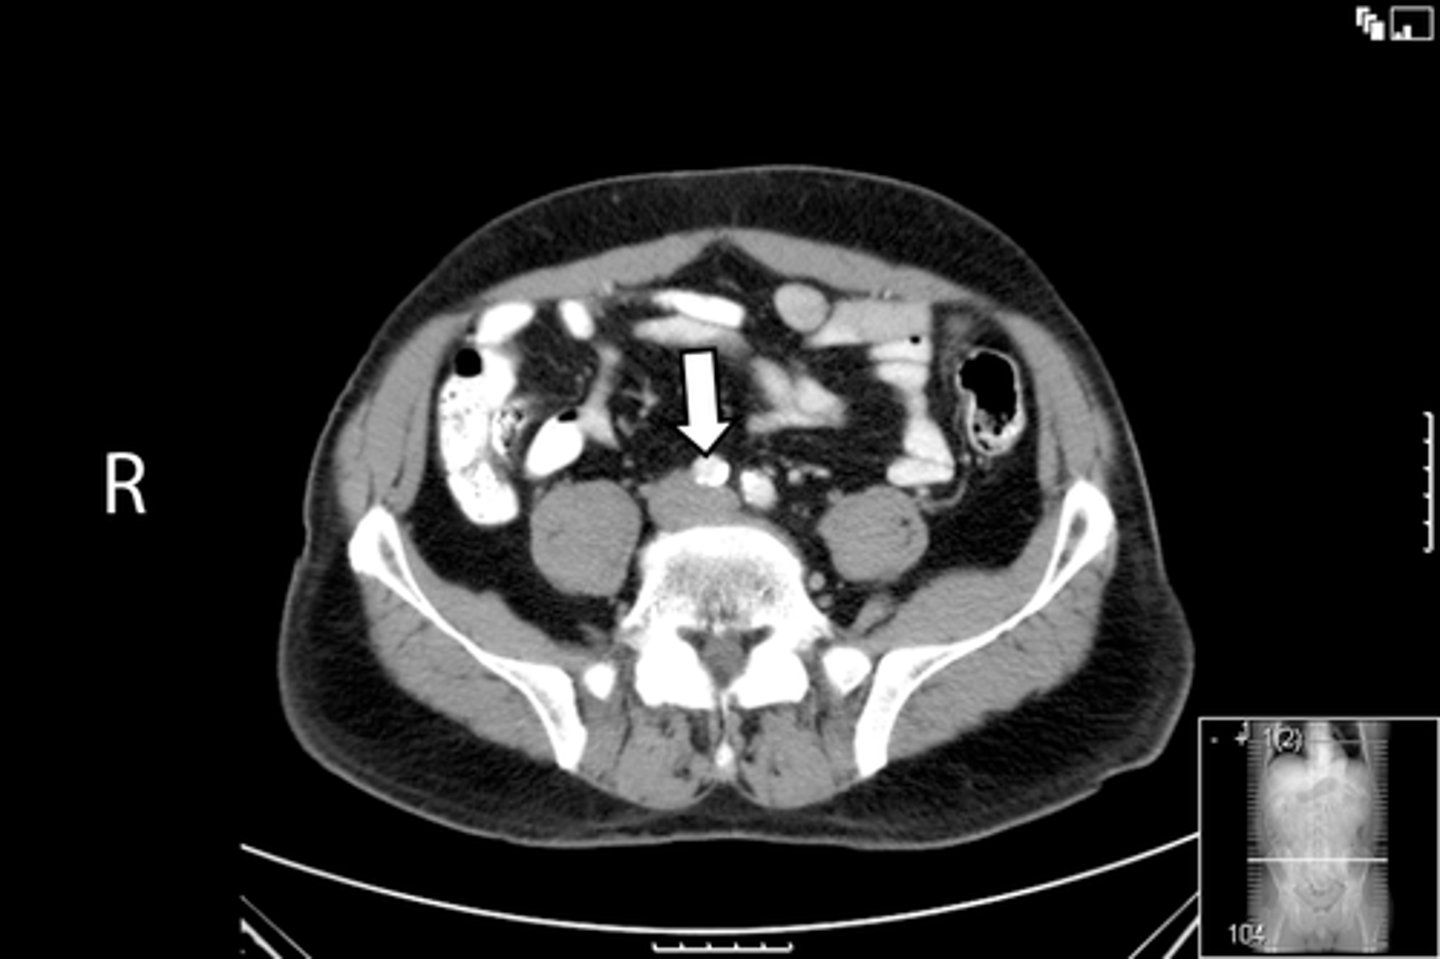

Axial male pelvis CT

What is the image?

55

Aorta

<p>What is indicated in the image?</p>

New cards

What is indicated in the image?

57

IVC

59

L psoas muscle

61

R psoas muscle

63

Terminal ilium